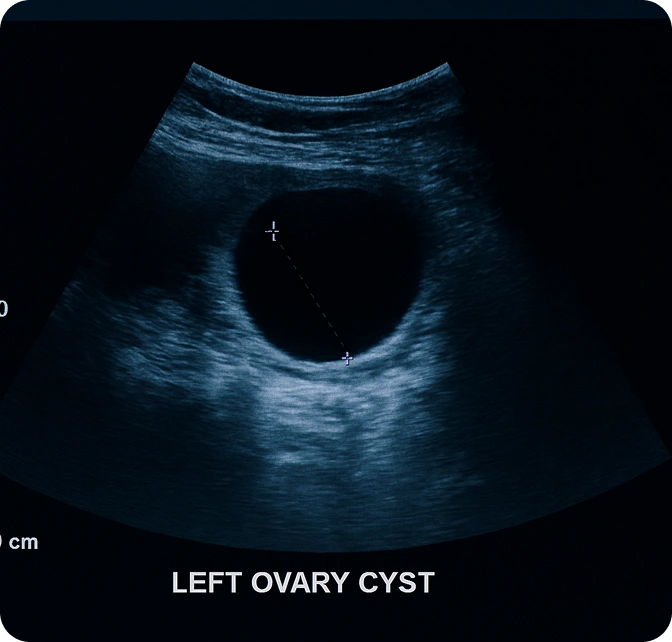

At Dr. Ashwini’s Scans and Labs, we use advanced ultrasound systems to capture detailed images of the uterus, ovaries, fallopian tubes, and bladder. This scan helps detect cysts, fibroids, fluid buildup, or other abnormalities at an early stage. Our focus is on providing clarity, comfort, and accurate imaging to guide effective medical care.

It helps identify ovarian cysts, uterine fibroids, or structural changes in the reproductive system with exceptional clarity. The scan can also detect fluid accumulation and other irregularities in the pelvic area.

Examines uterus, ovaries, fallopian tubes, and bladder precisely.

Identifies cysts, fibroids, and fluid buildup quickly.